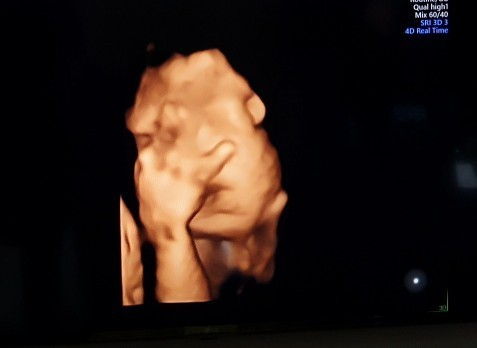

32w ผู้หญิงค่ะ ปิดหน้าตลอดจ้าา